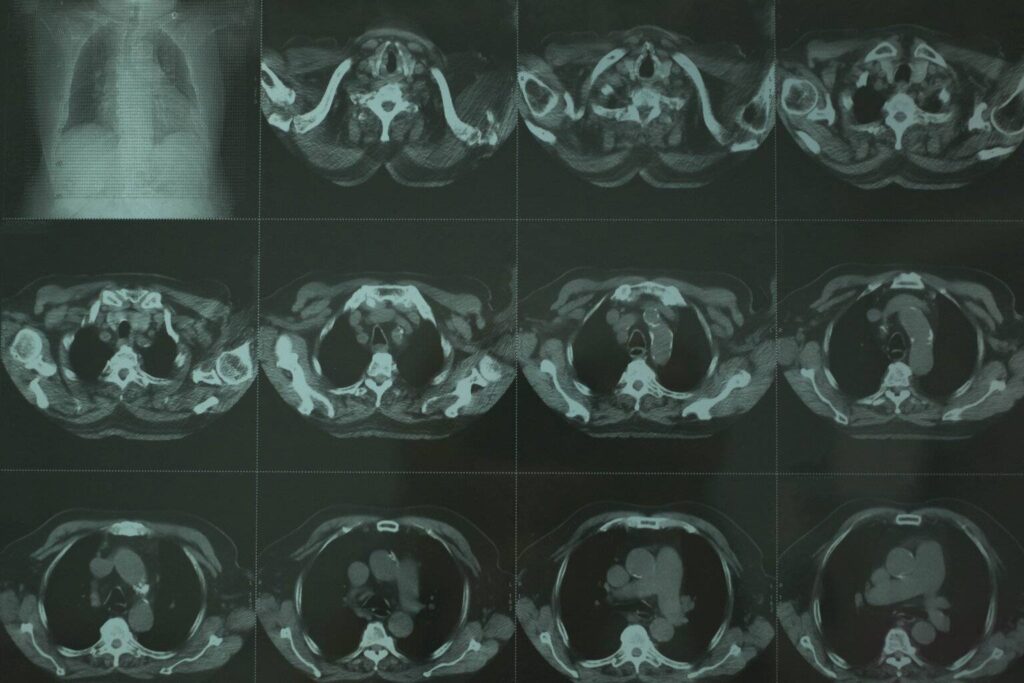

Scannen: Der CT-Scanner verwendet Röntgenstrahlen, um mehrere Bilder des Abdomens aus verschiedenen Winkeln aufzunehmen. Der Scanner dreht sich um den Patienten und nimmt dabei detaillierte Querschnittsbilder des Bauchraums auf.

CT Abdomen Befundung – CT Abdomen welche Organe sieht man?

- Die Leber – Befunde: Größe, Form, Beschaffenheit der Leber und Vorhandensein von Läsionen, Zysten, Tumoren, Abszessen oder Fettlebererkrankungen.

- Milz – Befunde: Größe, Form, Dichte der Milz und Vorhandensein von Anomalien wie Vergrößerung, Trauma oder Tumoren.

- Bauchspeicheldrüse – Befunde: Größe, Form und Struktur der Bauchspeicheldrüse sowie Nachweis von Tumoren, Zysten, Entzündungen (Pankreatitis) oder Anomalien der Gänge.

- Nieren – Befunde: Größe, Form und Lage der Nieren sowie Vorhandensein von Nierensteinen, Tumoren, Zysten, Infektionen oder anderen Nierenanomalien.

- Gallenblase – Befunde: Struktur und Größe der Gallenblase, Vorhandensein von Gallensteinen, Entzündungen (Cholezystitis) oder anderen Anomalien.

- Magen und Därme – Befunde: Darstellung des Magens, des Dünndarms und des Dickdarms (Kolon) auf Anzeichen von Entzündungen, Verstopfungen, Geschwüren oder Wucherungen.

- Nebennieren – Befunde: Nachweis von Nebennierenmassen, Tumoren oder anderen Anomalien.

- Blutgefäße – Befunde: Darstellung der großen Blutgefäße wie der Aorta und ihrer Verzweigungen, Untersuchung auf Aneurysmen, Dissektionen oder andere Gefäßprobleme.

- Lymphknoten – Befunde: Erkennung vergrößerter oder abnormaler Lymphknoten, die auf Infektionen, Entzündungen oder Krebs hinweisen können.

- Muskeln und Weichteile des Abdomens – Befunde: Beurteilung der Muskelstruktur, Vorhandensein von Massen, Hernien oder anderen Weichteilanomalien.

- Peritoneum und Mesenterium – Befunde: Beurteilung der Auskleidung der Bauchhöhle (Peritoneum) und der stützenden Membran (Mesenterium) auf Anzeichen von Entzündungen, Infektionen oder Tumoren.

- Beckenorgane (in einigen Fällen) – Befunde: Untersuchung der Beckenorgane wie Gebärmutter, Eierstöcke und Blase auf Anomalien, Zysten, Tumore oder andere Erkrankungen.